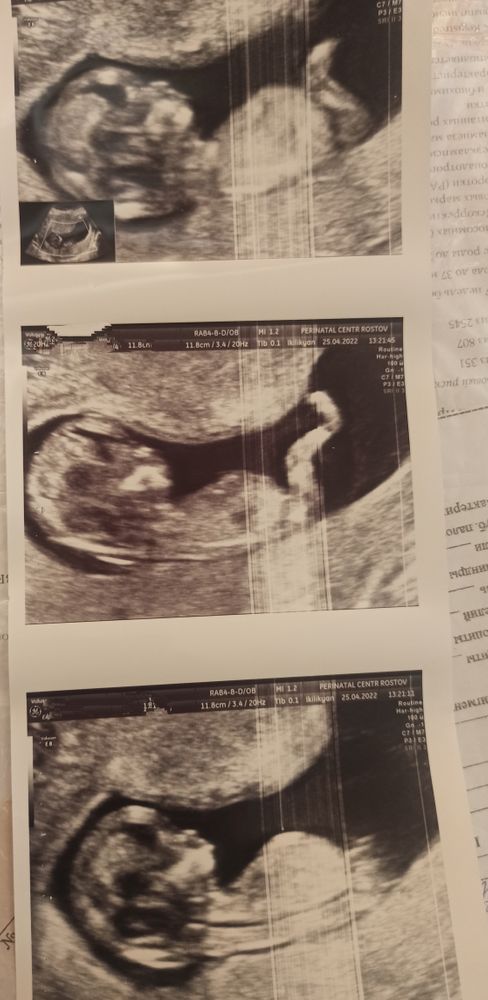

Срок 15,2 , на скрининге в 11,5 тоже предполагали 90% мальчик

Хочу на выходных объявить родным пол ребенка. Все очень ждут мальчика💙 Доктор сказал 100% сын. А очень рада, но очень боюсь ошибки... Хотелось бы послушать ваше мнение. Я даже маме пока не сказала... Хотя хочется уже всем объявить о своем счастье💞

Ну какая тут ошибка, все же видно на снимке, у девочек таких бубенчиков не бывает))

Смотрю, Вы пост переименовали))) Парень у Вас, видно же))) Вон мошонка и перчик сверху😊